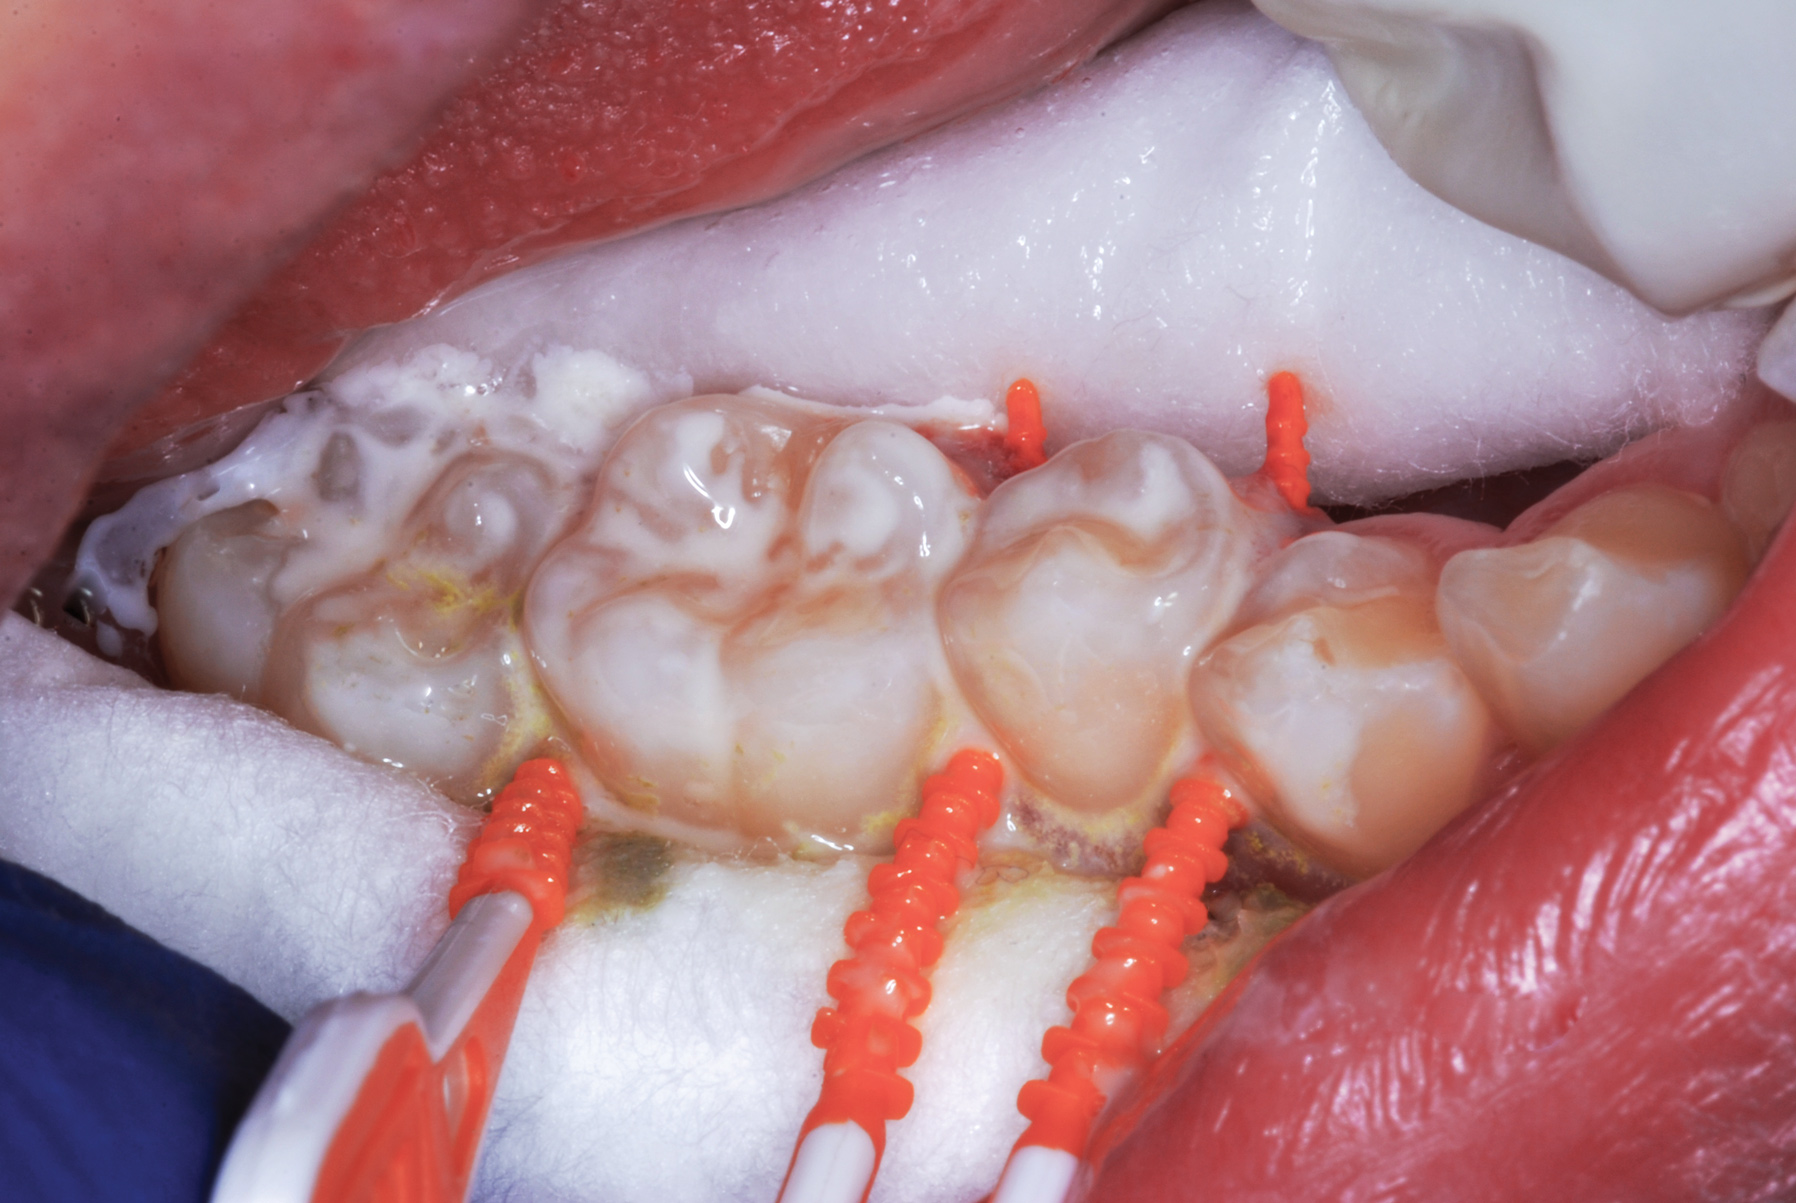

Fig 4. Three thin soft dental picks were used simultaneously for SDF proximal surface saturations in a teenaged patient (Fig 3). After 60 seconds, the treated regions were covered with 5% fluoride varnish (Fig 4). A comparison can be seen of pre-SDF-treatment bitewing films (Fig 5) and 8-month post-SDF bitewing films (Fig 6) for the patient shown in Fig 3 and Fig 4. Radiolucencies were similar or improved, except for contact of maxillary first and second molars.

Figure 4

Interproximal insertion of SDF is demonstrated in different patients in Figure 3 through Figure 11. Various diameters and brands of soft dental picks may be used depending on the closeness of the proximal surfaces and ease of insertion; for example, some picks are designed for use in wider spaces between teeth. This protocol also offers versatility. Figure 3, for example, shows the simultaneous use of three thin soft dental picks to saturate proximal surfaces with SDF in a teenaged patient; the treated regions were subsequently covered with fluoride varnish (Figure 4). This patient was initially treated in April 2019 (Figure 5), with an identical re-application 3 months later. As shown in Figure 6, the December 2019 bitewing film revealed good results with the possible exception of the contact regions of the maxillary first and second molars. New SDF application was completed in the December appointment.